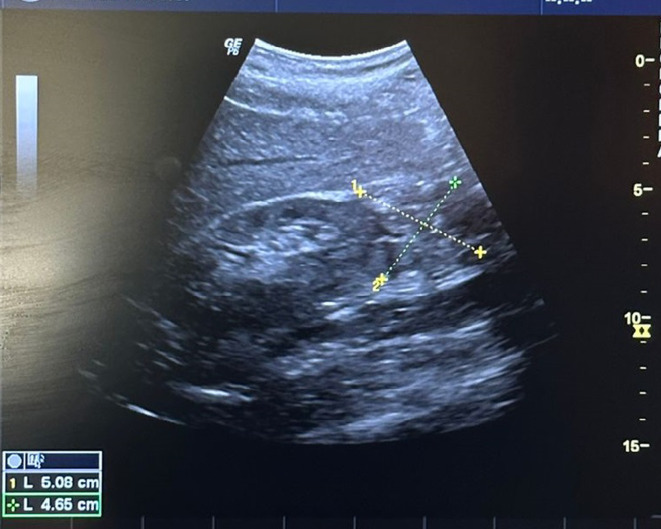

Tuberculosis (TB) remains one of the world's leading causes of morbidity and mortality. It occurs in both pulmonary and extra-pulmonary forms. Primary iliac bone TB remains a rare clinical entity, even in endemic areas. The diagnosis of the disease can be challenging due to its similarity to other bone diseases. We report a rare case of primary iliac bone TB in a 63-year-old patient who was on peritoneal dialysis and had a medical history of hypertension and type II diabetes, which was complicated by diabetic retinopathy and diabetic kidney disease. Magnetic resonance imaging revealed osteomyelitis in the iliac bone, while real-time polymerase chain reaction using the GeneXpert® system on a gluteal collection sample confirmed the diagnosis of TB. The integration of advanced molecular tools, such as GeneXpert®, represents significant progress, enabling rapid and accurate diagnosis of TB and facilitating early initiation of treatment.

Abstract Image